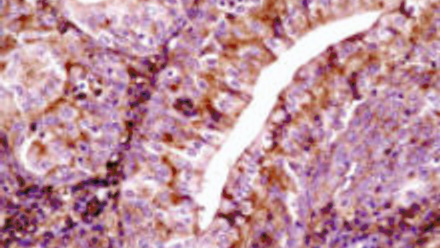

This issue of Microbiology Today is a ‘virology special’; this is in part to recognise the contribution of this year’s SGM Prize Medal winner, Harald zur Hausen, and his ground-breaking contributions to understanding the link between viruses and cancer.